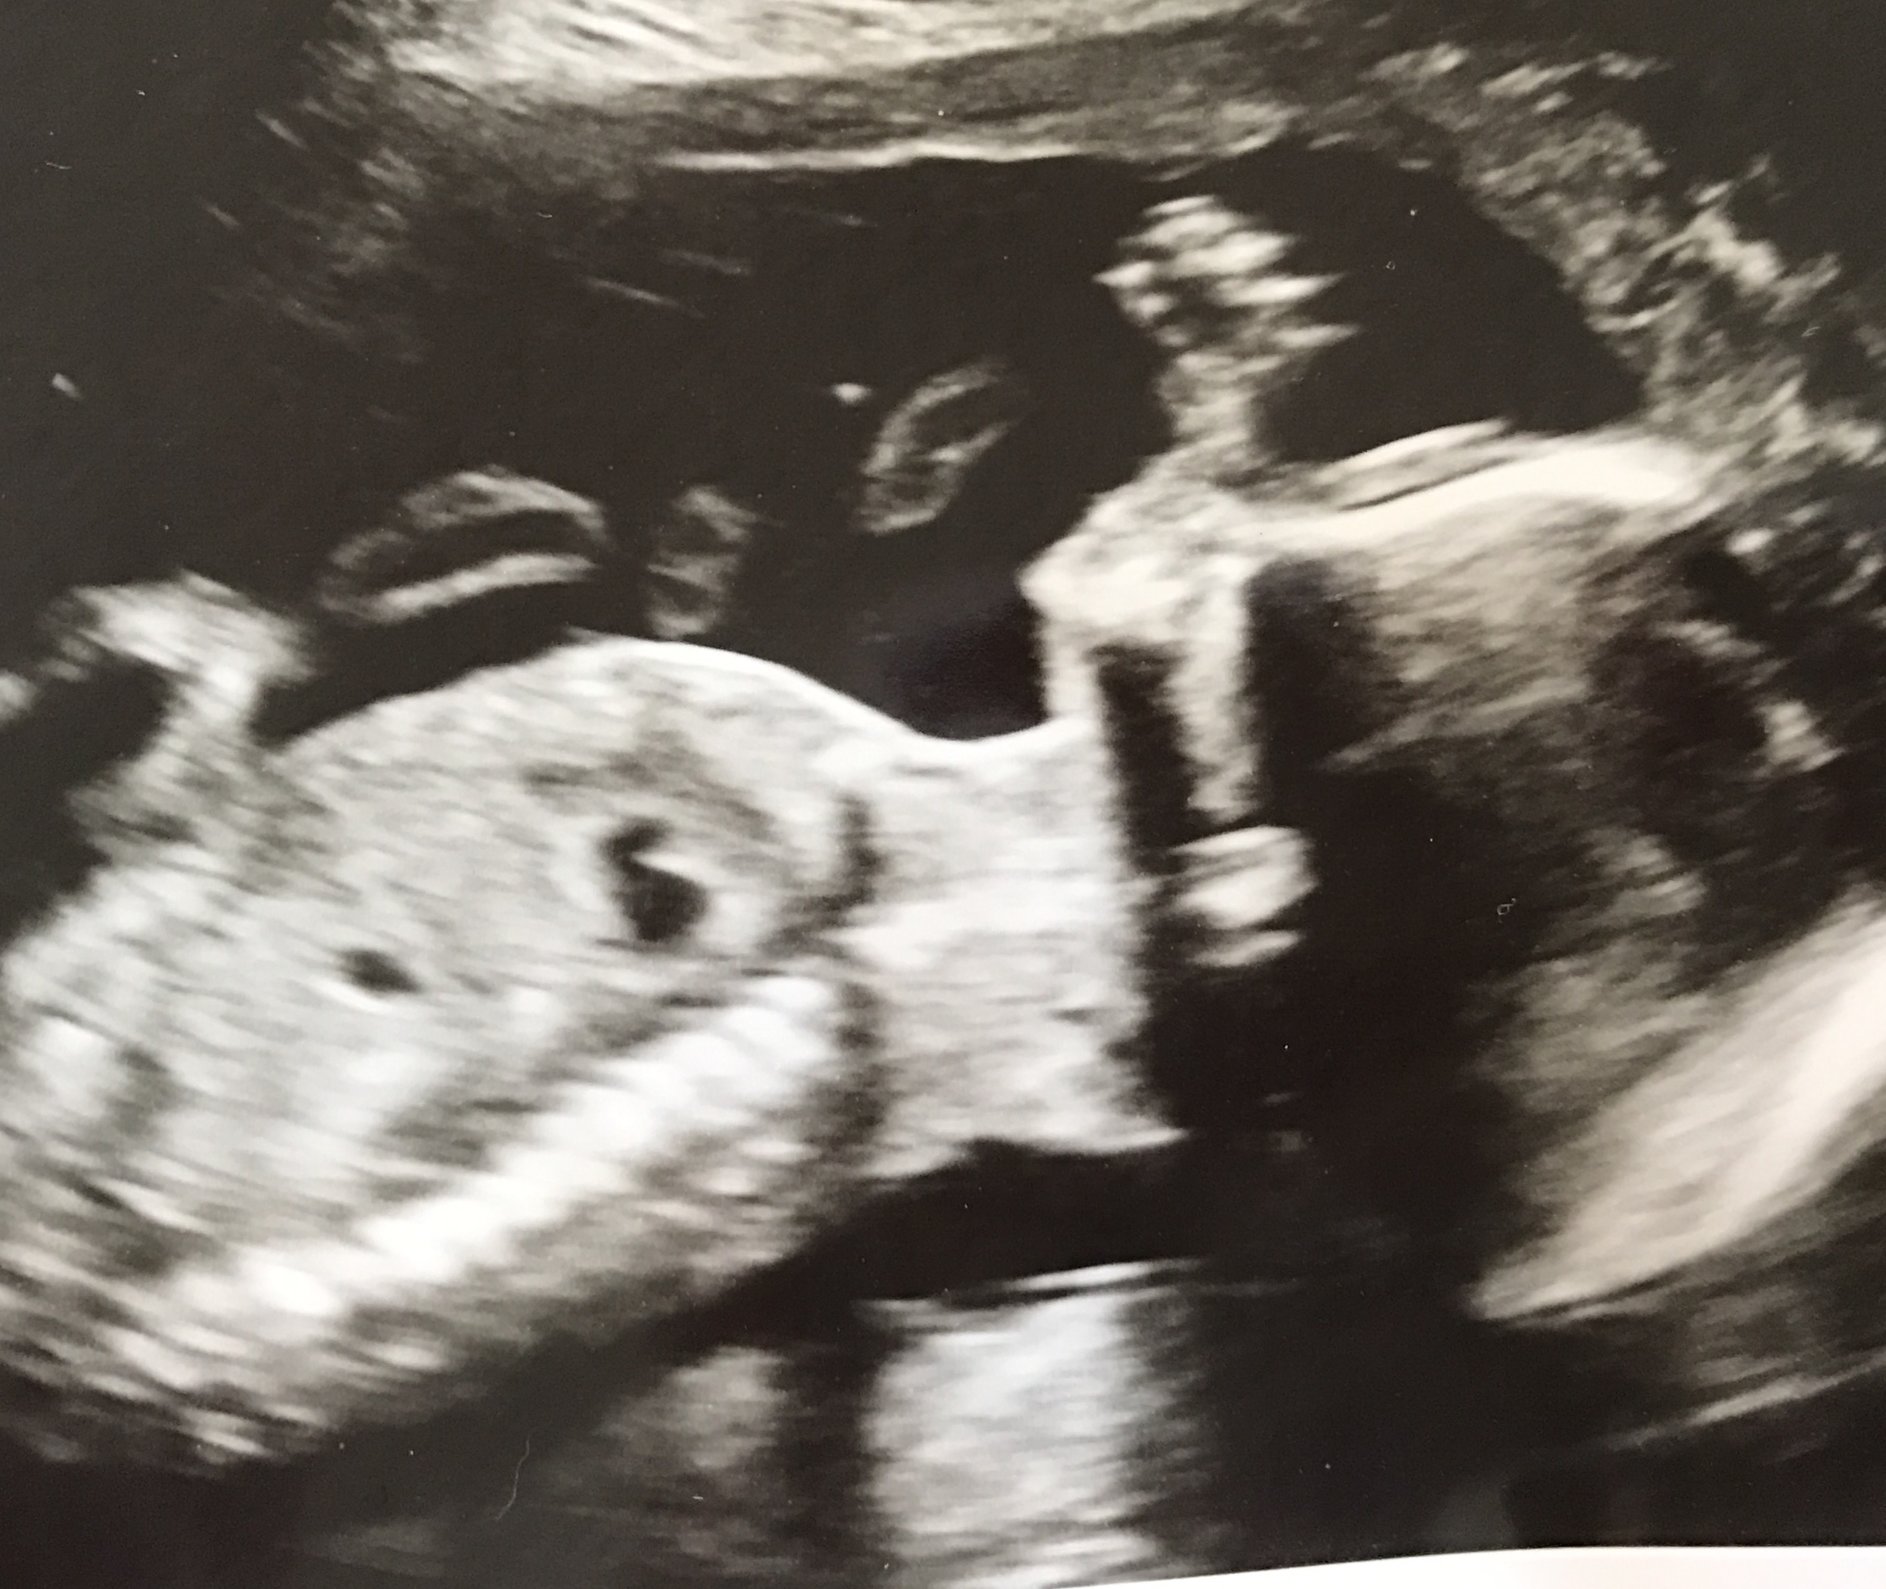

Here's our baby boy from our AS yesterday! I was 20w3d. MD said everything looks great and although they didn't change my due date, the report indicates a due date of 2/27 instead of 3/5. I'll take it! I was crying my eyes out when I saw that little face! We are in love!